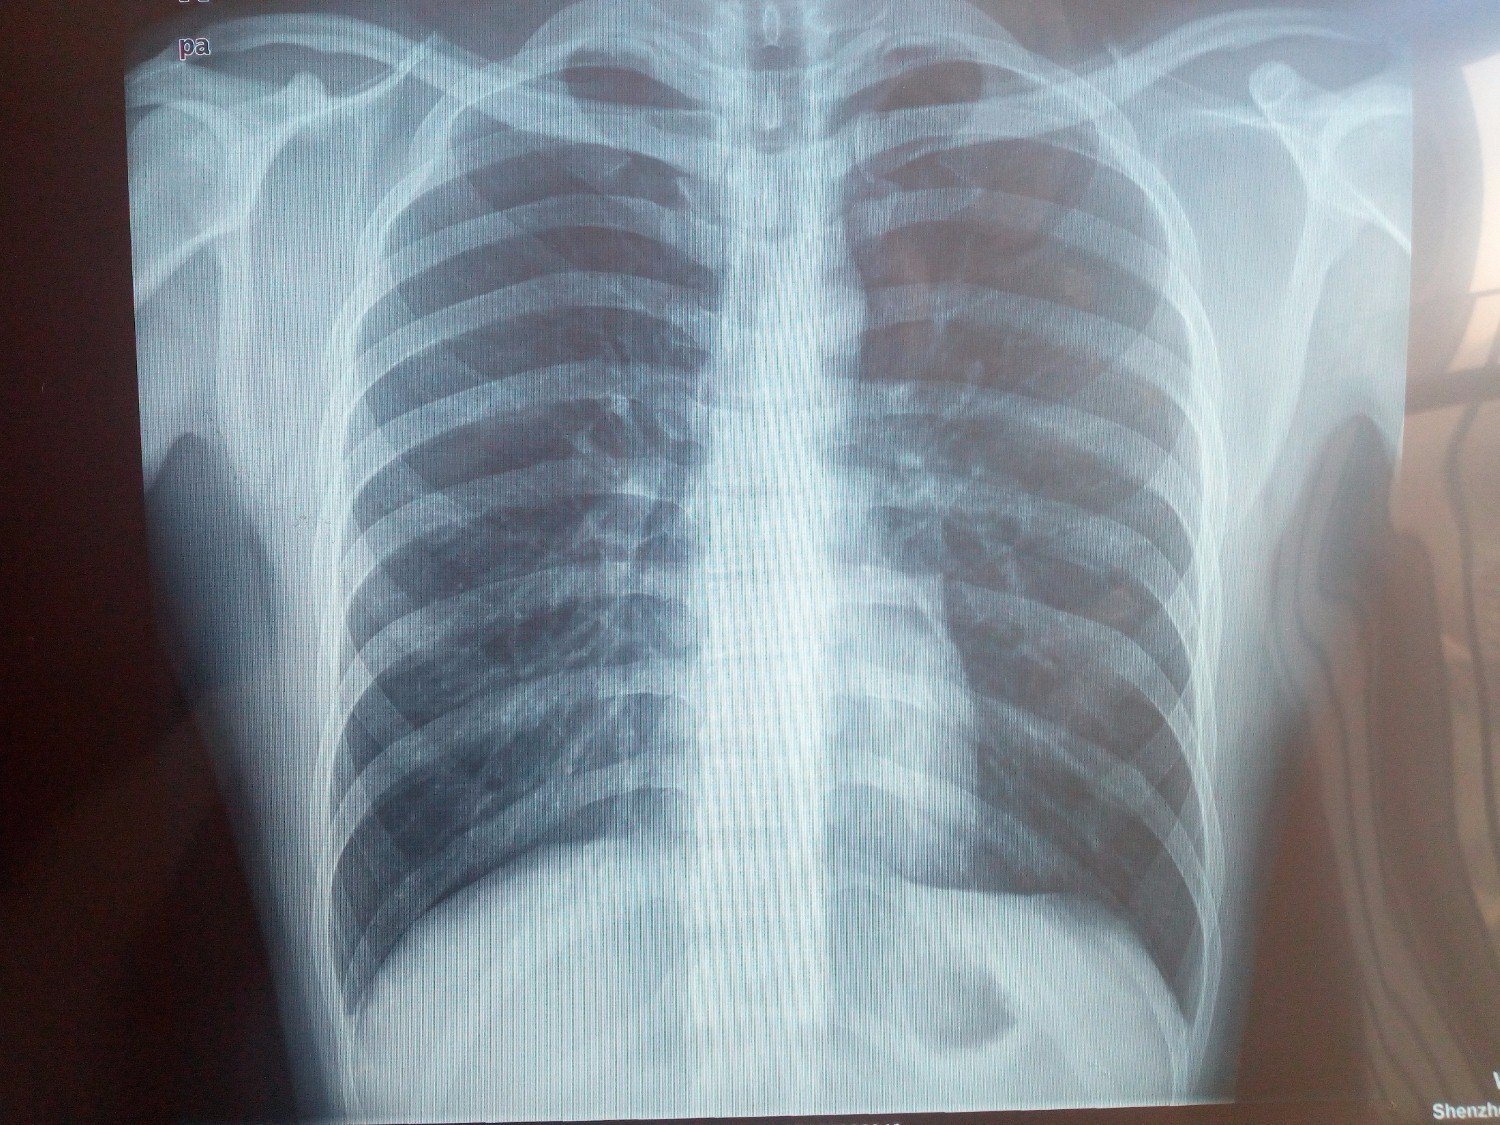

1.X线片(膝关节为例)

一张膝关节X片一般包括膝关节正位和膝关节侧位片。片子上一般标记有医疗机构、姓名、性别(W:女;M:男)、侧别(L:左;R:右)、时间,其他标记的有标尺、窗口等。